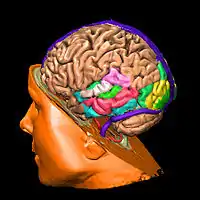

Advancements in imaging technology has propelled our understanding of the brain as it pertains to language and disorders such as aphasia. Voxel-based Lesion Symptom Mapping (VLSM) in particular, has allowed for medical professionals to determine more specifically where brain lesions lie and the tasks that are impaired because of them. VLSM's ability to identify white matter regions which can play causal roles in certain cognitive domains allows for professionals closely identify these problem regions. A 'voxel' is the three dimensional analog of a pixel and represents a volume of 1 cubic millimeter; The image produced displays 3 dimensional picture of the human brain as depicted in the picture to the right. Studies using VSLM have suggested that language functions are not as localized as the Geschwind model posits it to be. [4]